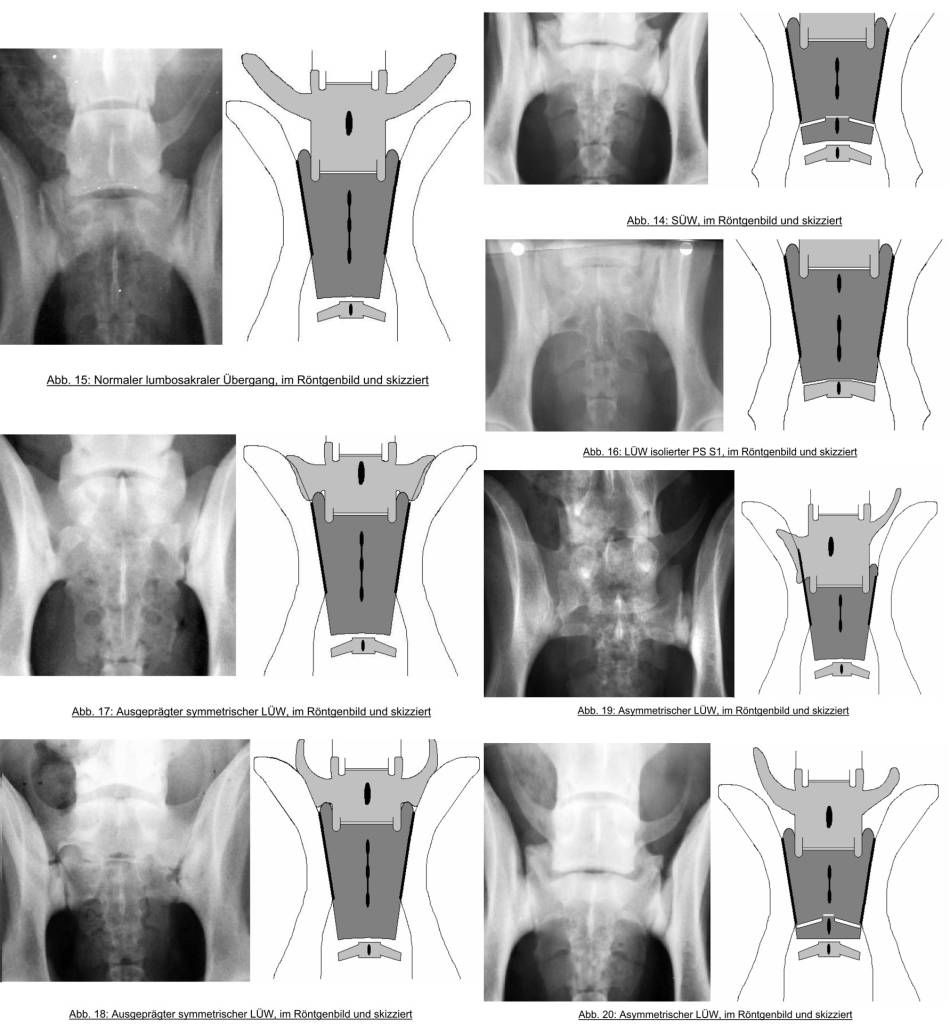

Übergangswirbel

Definition

- Wirbel, der Eigenschaften von 2 aneinandergrenzenden Wirbelsäulenabschnitten hat

- lumbosakraler ÜW: Lumbosakrale Stenose, CES, BSV, Schrägstellung Becken

Formen